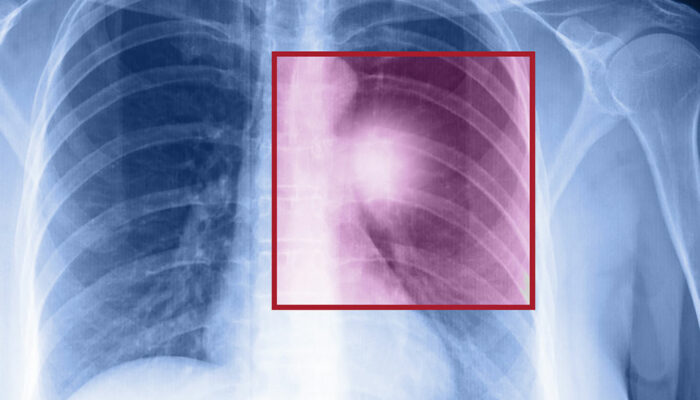

Lung cancer – Types, symptoms, and causes

When the cells in the lungs begin to abnormally multiply and grow, it results in cancer. Lung cancer is one of the leading causes of death in the world. And the risk of suffering from this life-threatening disease is even higher when one is a smoker. Herein, we discuss the various factors that come into play when it comes to lung cancer.